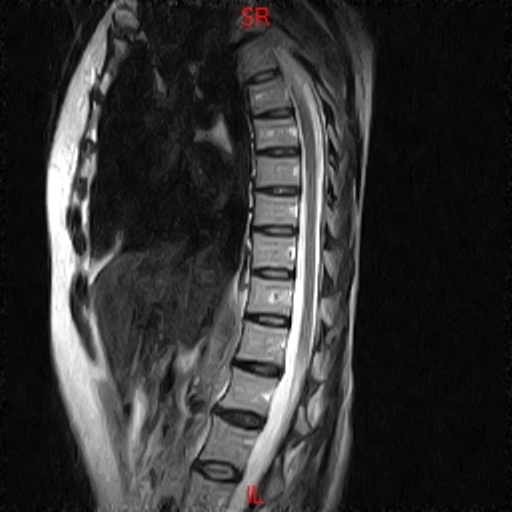

• Resonancia NORMAL COLUMNA DORSAL T2 SAGITAL